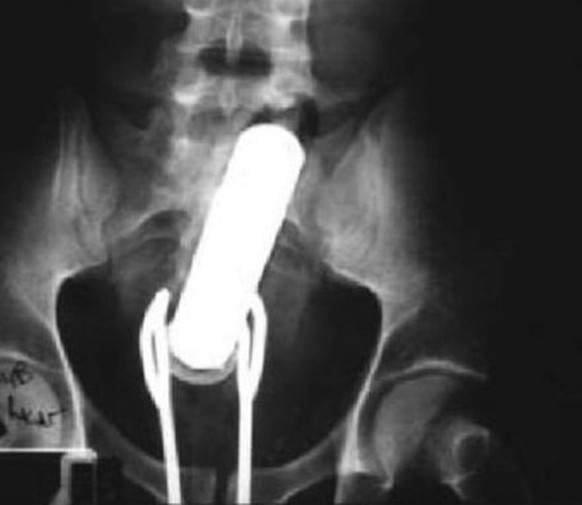

Sein Röntgenbild zeigt ein Mobiltelefon im Mastdarm. Wie kommt's?

Er habe geduscht; ja, mit dem Handy (das wasserfeste Samsung Galaxy S5 gab es da noch nicht) und dann sei er auf den Fliesen ausgerutscht und auf das Telefon gefallen – und schwups war es im Hintertürchen verschwunden.

Während die Ärzte den Fremdkörper herausmontierten, soll es noch dreimal geklingelt haben. Wir wollen hoffen, dass wenigstens der Klingelton nicht peinlich war.